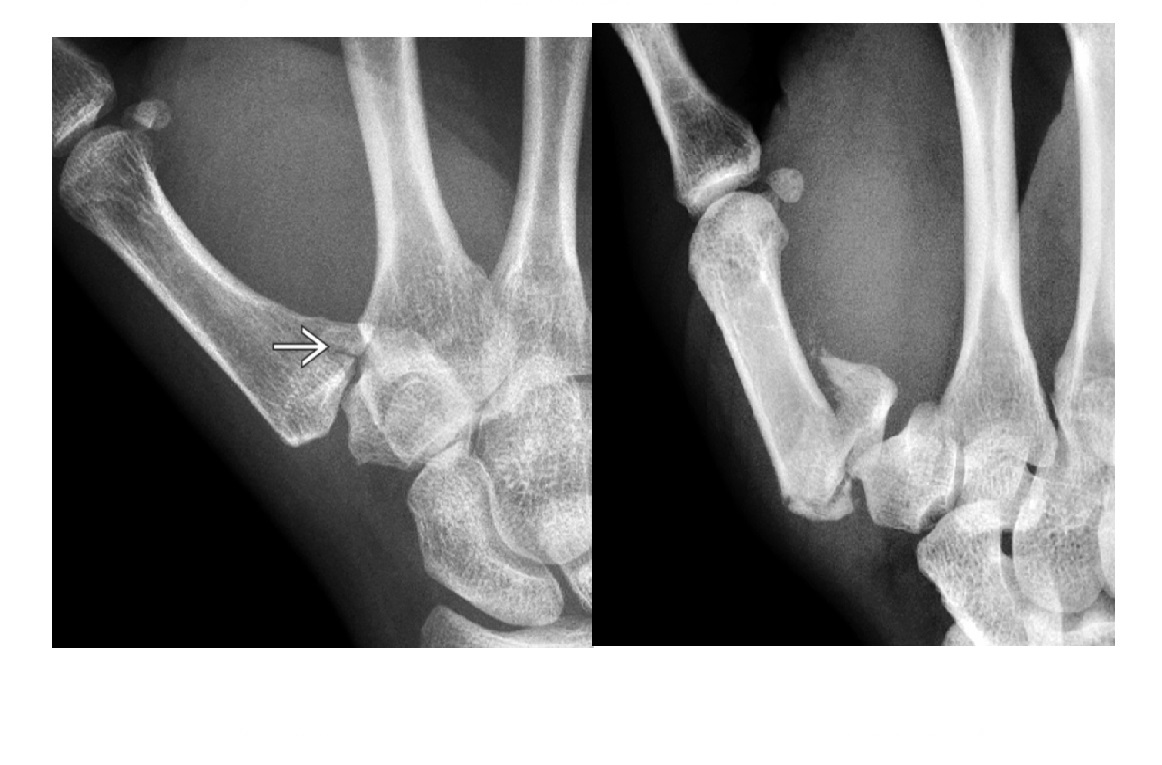

Bennets

Fracture base of the first metacarpal

Pull of the abductor pollicus longus (APL tendon causes dorsolateral dislocation

Nb a comminuted # base of 1st metacarpal = ROLANDO

Gamekeepers

Avulsion fracture of the base of the proximal first phalanx

Ulnar collateral ligament disruption

STENER lesion = when adductor tendon gets caught in the torn edges of the UCL = Surgery